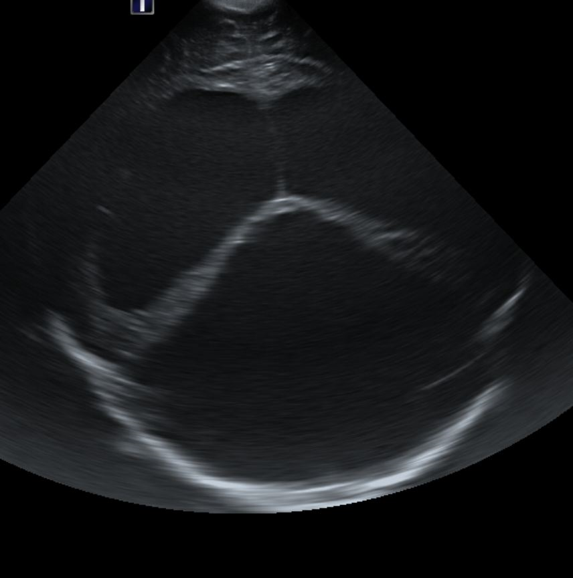

CSF spaces/ventricular system

There is a prominence of the extra axial fluid spaces. [Yes/No]

There is prominence of the ventricular system. [Yes/No]

The lateral ventricle/s are dilated. [Yes/No]

The third ventricle is dilated. [Yes/No]

The 4th ventricle is dilated. [Yes/No]